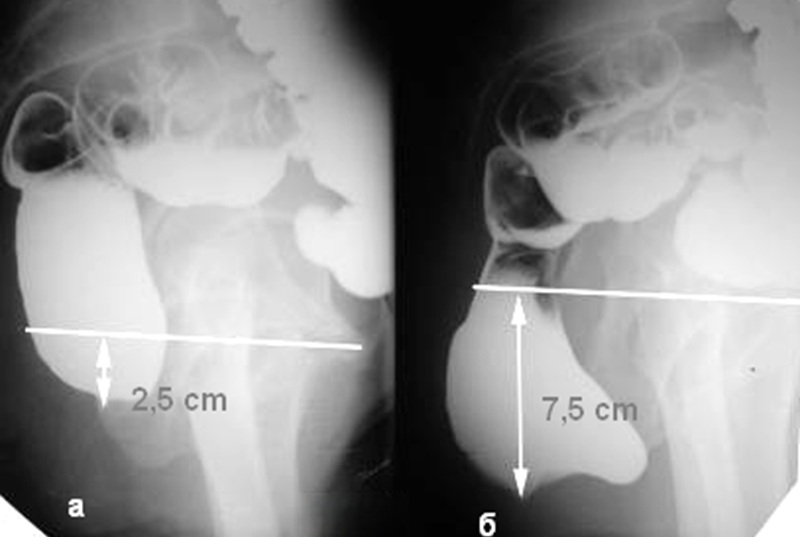

- Фиксация результатов. Полученные данные фиксируются в виде серии снимков и видеозаписи с высокой частотой кадров, которые будут подробно проанализированы врачом-рентгенологом после завершения процедуры. Врач измеряет ключевые параметры: аноректальный угол, длину анального канала, время эвакуации контраста, наличие ректоцеле и его глубину.

В ходе проктографии используется рентгеновское излучение, контрастные вещества и специальные приборы для создания серии снимков и видеозаписи дефекации. Этот метод позволяет выявить различные аномалии, нарушения или дефекты в работе кишечника, включая ректоцеле, инвагинацию, анизм и энтероцеле. В отличие от стандартной колоноскопии, которая оценивает только состояние слизистой оболочки, проктография дает функциональную оценку всего тазового дна в динамике.